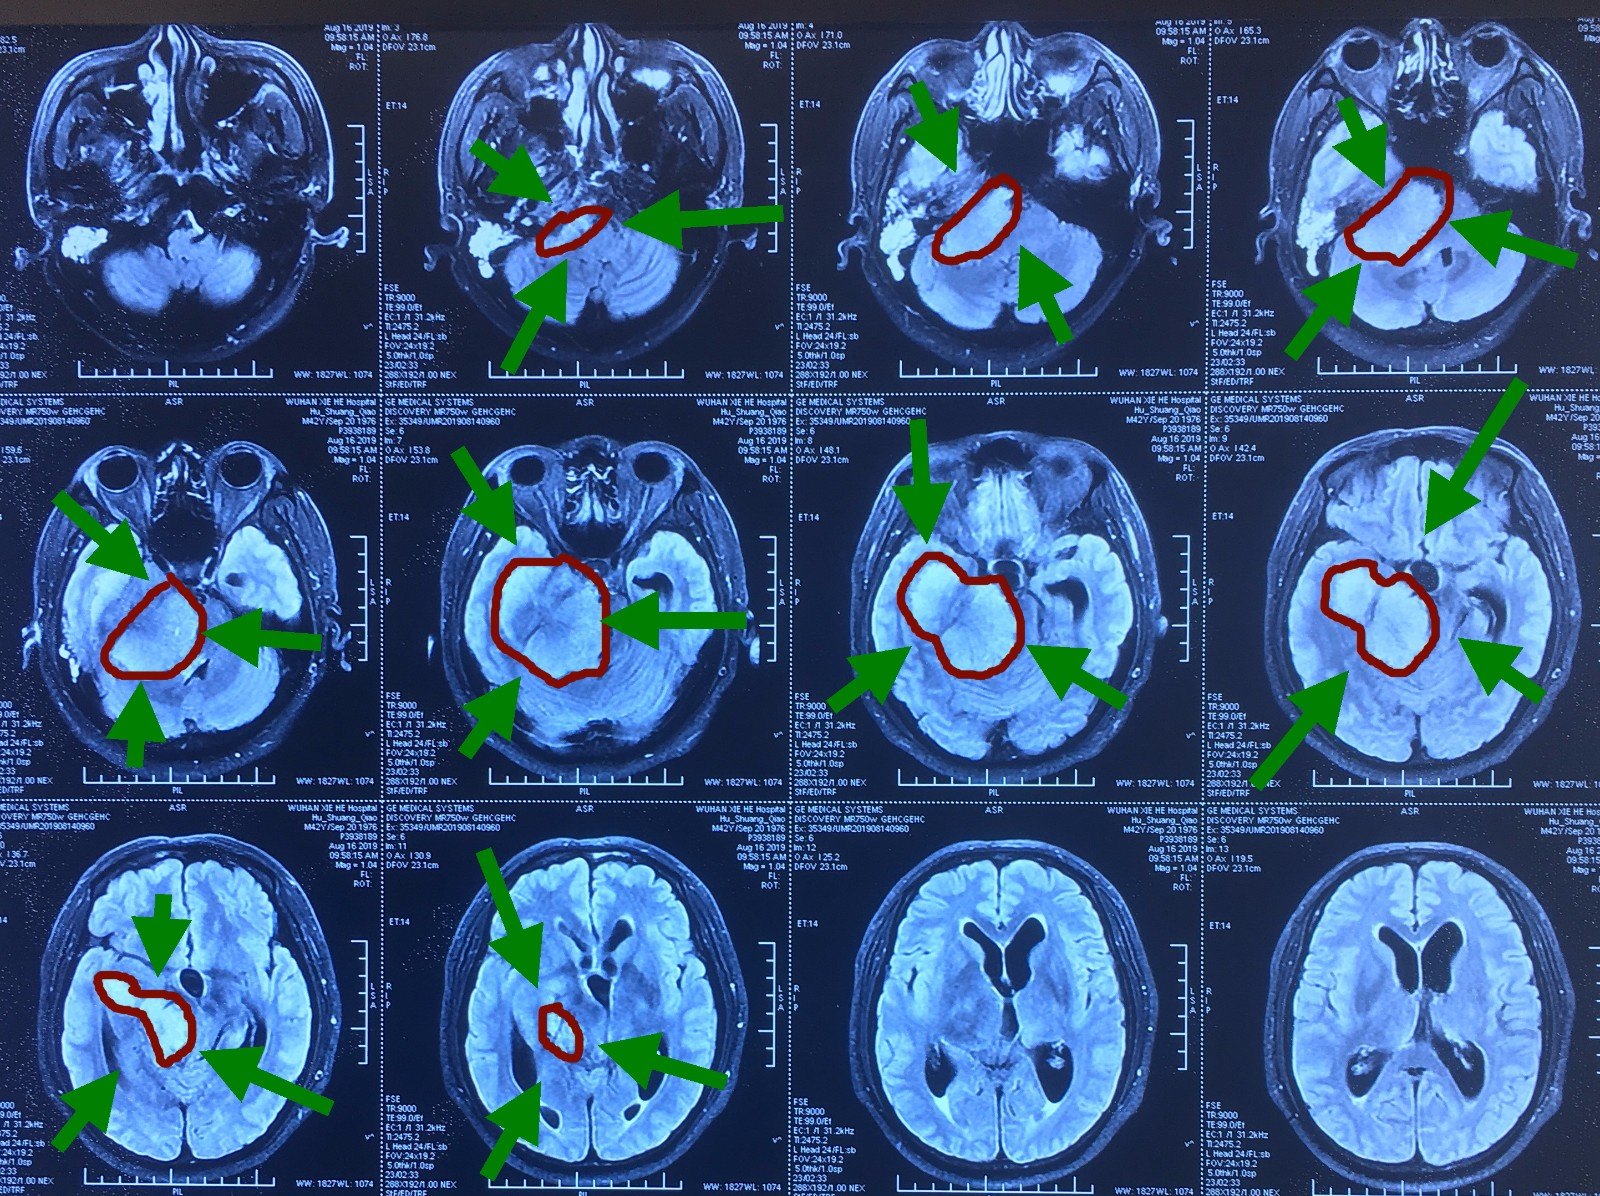

病情复发与转院建议患者父亲2016年底在安徽医科大学第一附属医院由王先祥医生做了脑膜瘤手术,手术很成功但后来复查发现脑膜瘤复发合肥的教授医生考虑到合肥没有做手术所需的某种检测辅助仪器,手术成功率很低,因此建议患者前往北京天坛医院治疗北京求医过程挂号与初诊2021年3月24日,挂了北京天坛医院。